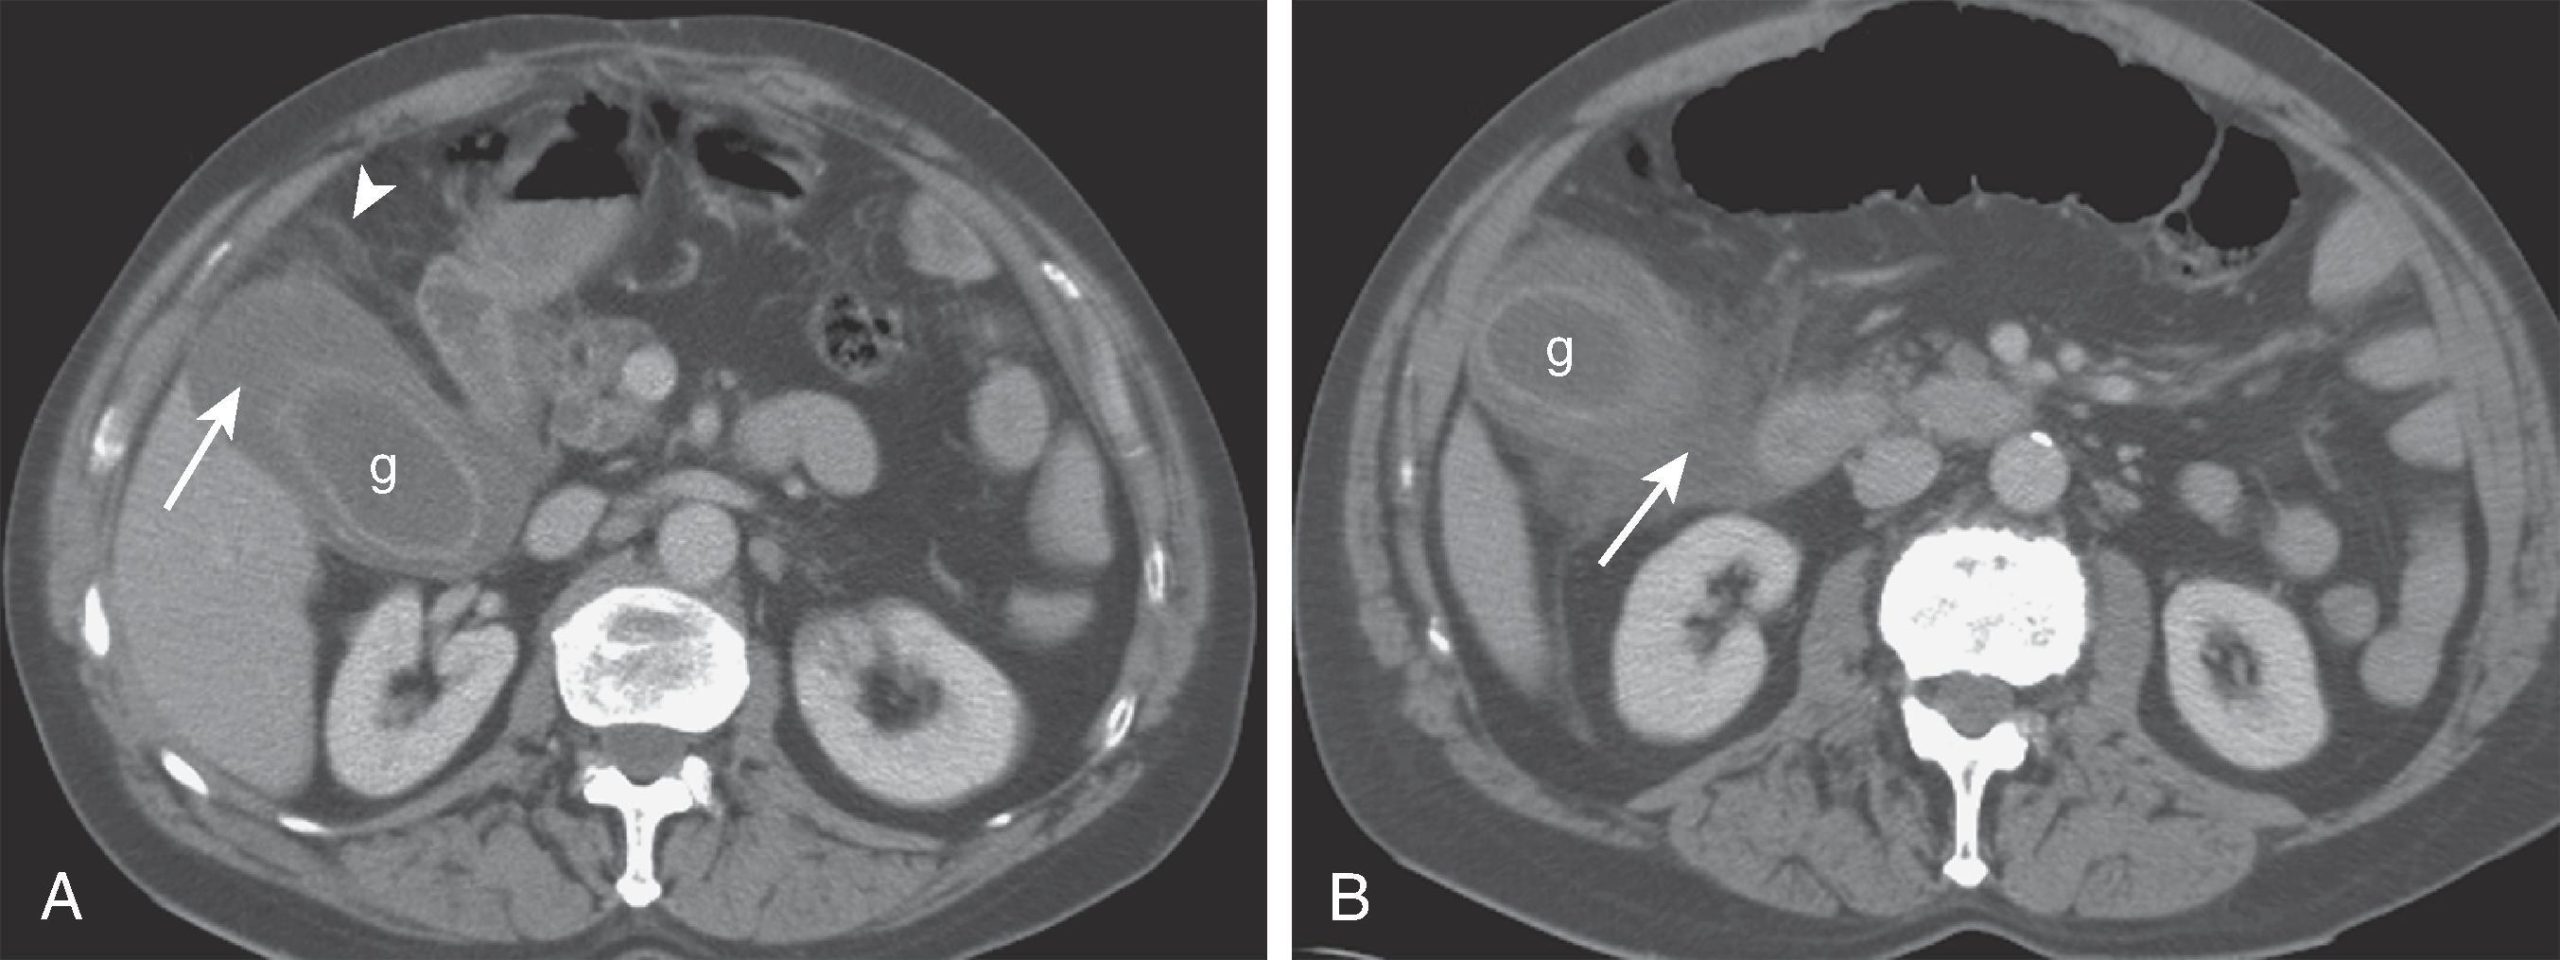

هیدروپس کیسه صفرا

در زمینه وجود سنگهای مجرای صفراوی (Choledocholithiasis) یا تغییرات زخمی، مثلاً ناشی از التهاب، ممکن است مسیر جریان صفرا مسدود شود و دیواره کیسه صفرا کشیده شود (هیدروپس کیسه صفرا). این وضعیت میتواند با درد همراه باشد و به صورت حاد، متناوب یا مزمن بروز کند.

اغلب هیدروپس کیسه صفرا اولین علامت سنگهای صفراوی است. در موارد نادر، تومورها نیز میتوانند جریان صفرا را مسدود کنند. چون علت اصلی اغلب سنگها هستند، در چنین مواردی برداشتن کیسه صفرا درمان انتخابی محسوب میشود.